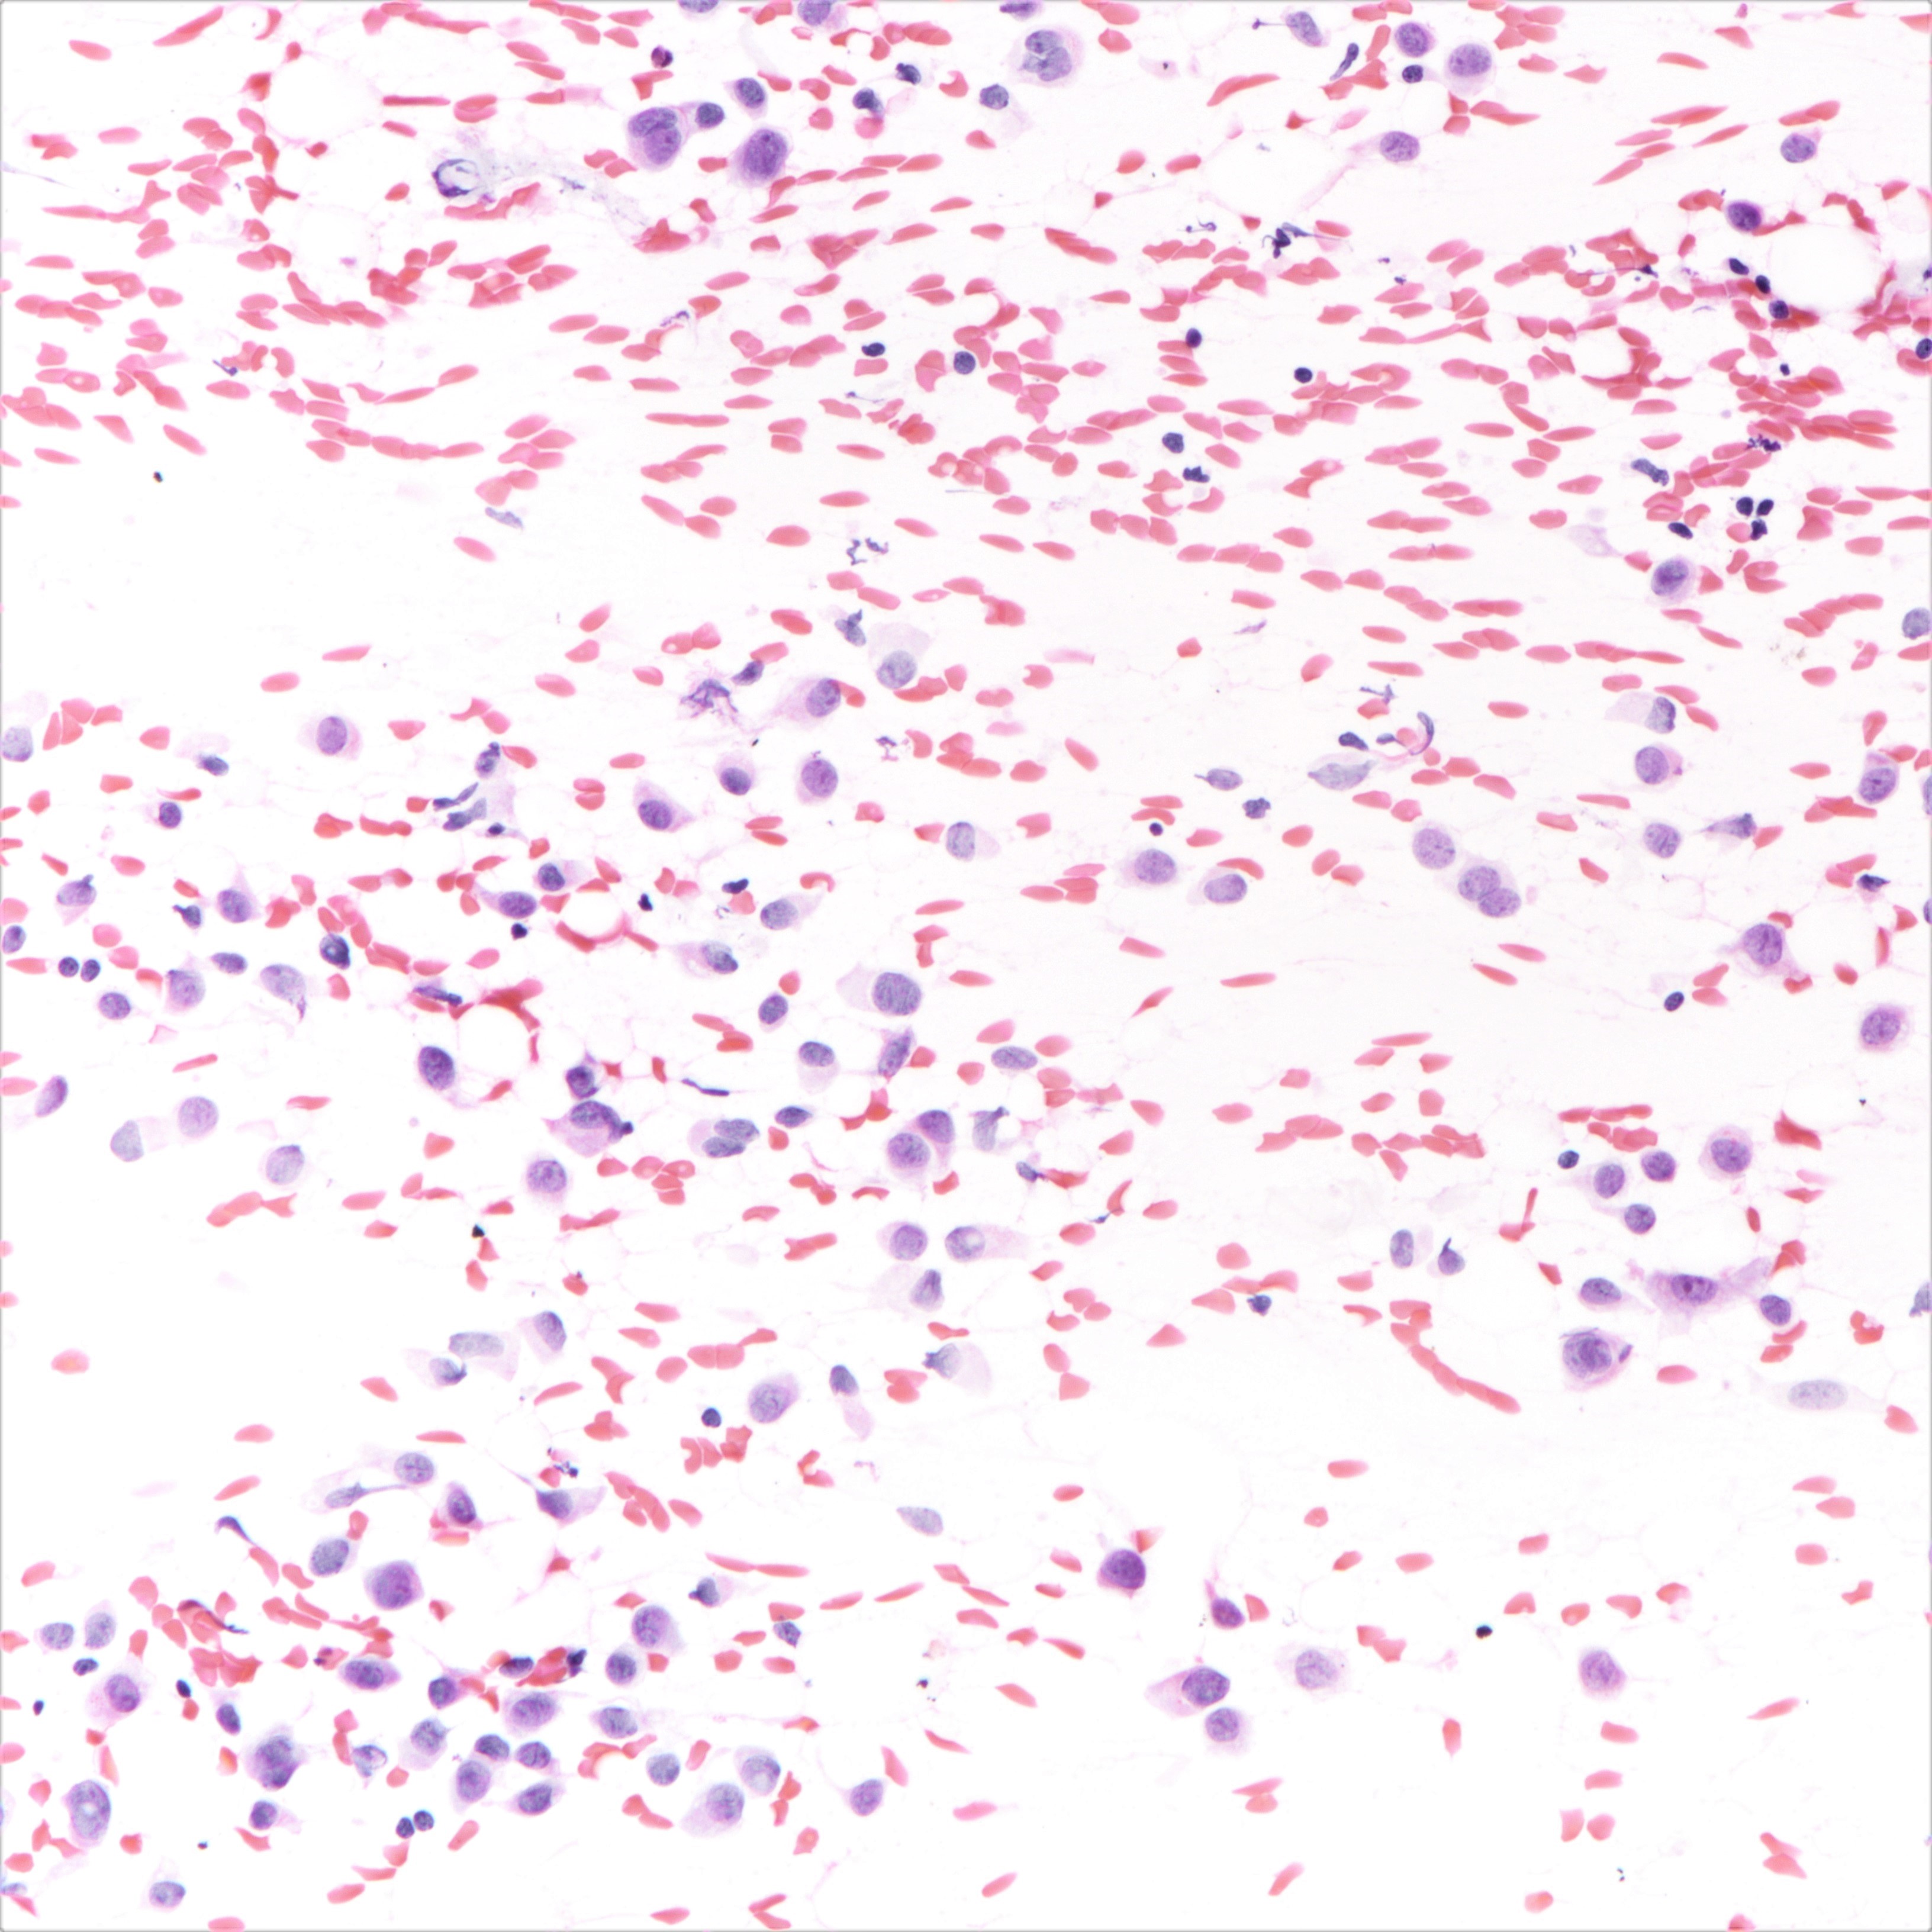

Cytology description

- Cellularity can be low

- Tumor cells arranged in chains, single files or as single cells

- Tumor cells arranged in small chains are helpful clues

- Nuclear atypia mostly mild

- Nuclei round to oval and eccentric

- Cytoplasm scanty with a high nuclear / cytoplasmic ratio

- Occasional intracytoplasmic vacuolations may be seen

- Cytologic features can resemble mesothelial cells in effusion fluid (Diagn Cytopathol 2012;40:311)

Cytology images